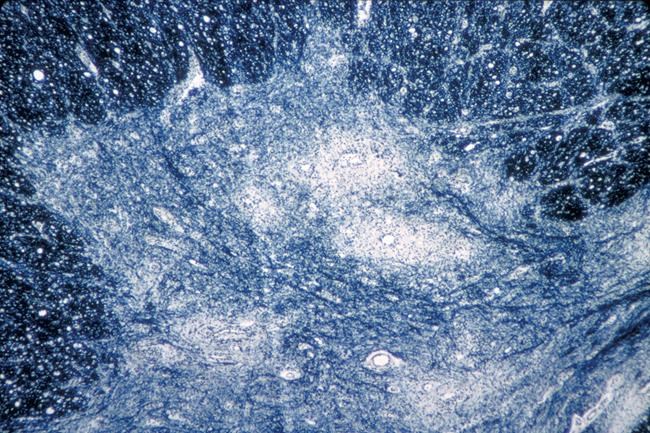

Polio is considered very contagious and spreads mostly from person to person, through contaminated water and via fecal particles.